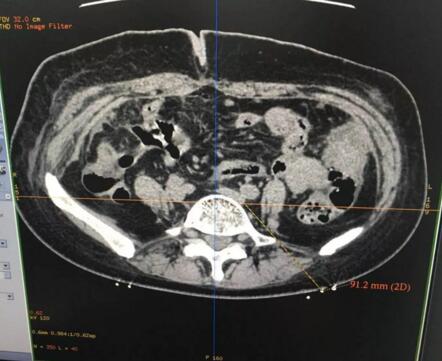

手術(shù)當(dāng)日,在放射科全力配合下,王鑫主治醫(yī)師順利完成了CT引導(dǎo)下上腹下神經(jīng)叢毀損術(shù)。術(shù)中采用“雙針會(huì)合法”,雙側(cè)穿刺針在CT精準(zhǔn)導(dǎo)航下達(dá)腹主動(dòng)脈兩側(cè),造影劑注射掃描見(jiàn)造影劑彌散良好,利多卡因阻滯試驗(yàn)?zāi)芨采w疼痛區(qū)域,注射10ml無(wú)水乙醇進(jìn)行神經(jīng)毀損……

術(shù)中精準(zhǔn)定位